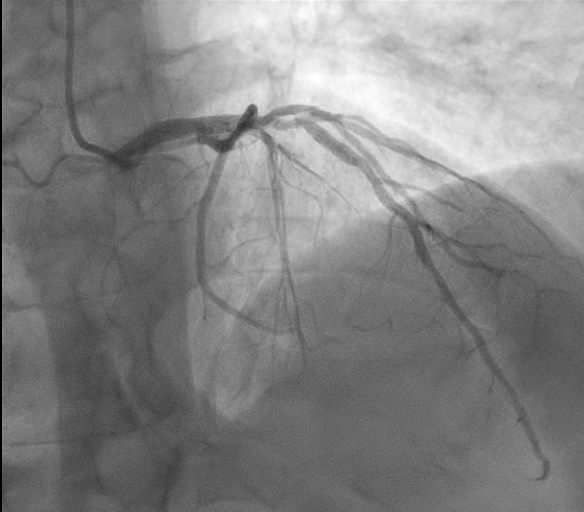

We report the case of a 65-year-old man presenting with chest pain occurring the night before. ECG showed negative T waves in the inferolateral leads. Laboratory revealed rising troponin (0.139 to 0.688 ng/mL). Transthoracic echocardiography demonstrated preserved systolic function without regional wall motion abnormalities (ejection fraction 55%). The day after, complete normalization of the ECG was observed. Patient underwent coronary angiography which revealed an intermediate stenosis of the left anterior descending artery (LAD) not functionally significant (iFR 0.91, FFR 0.87) (Fig. 1). 24-hour Holter ECG monitoring documented episodes of atrial fibrillation. He was discharged on day five with a diagnosis of myocardial infarction with non-obstructive coronary arteries (MINOCA) and referred for cardiac magnetic resonance (CMR). Discharge therapy included Aspirin, Edoxaban and Rosuvastatin/Ezetimibe. Subsequent CMR revealed myocardial edema and late gadolinium enhancement with a transmural ischemic pattern involving the basal inferolateral and anterolateral segments and the apical lateral segment and microvascular obstruction in the basal inferolateral segment, consistent with transmural myocardial infarction (Fig. 2). A subsequent review of the coronary angiogram identified an intermediate, hazy lesion in the proximal circumflex/obtuse marginal branch, compatible with the culprit lesion (Fig. 3). The patient was contacted and clopidogrel 75 mg daily was added, resulting in triple antithrombotic therapy for one month. At 30-day follow-up, the patient remained asymptomatic. This case highlights the pivotal role of CMR in clarifying the diagnosis and guiding therapy in MINOCA, even when the underlying etiology remains uncertain between coronary embolism and unstable plaque.